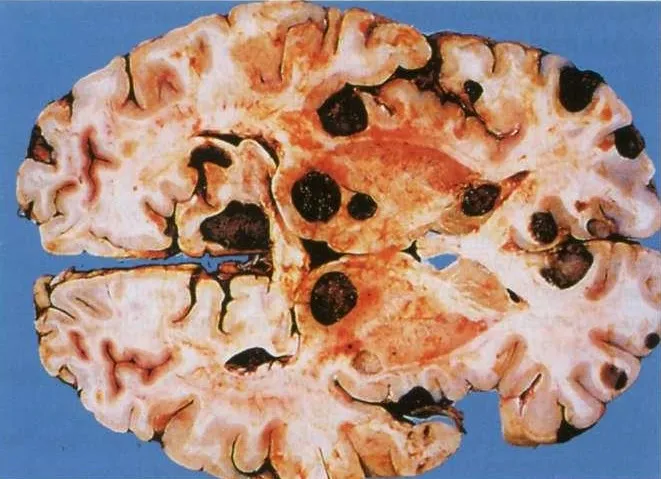

Przekrój horyzontalny przez mózg człowieka z obecnością licznych guzów przerzutowych czerniaka.

Ryc. G – Przekrój horyzontalny przez mózg człowieka. Uwidocznione są liczne przerzuty czerniaka, które dokonały destrukcji m.in. wzgórza i głowy jądra ogoniastego. Prócz jąder podkorowych przeżuty zlokalizowały się w obrębie płata czołowego. Warto dodać, że w przypadku nowotworów przerzutowych mózgu wyraźne są granice między tkanką zdrową a nowotworową. Nie dzieje się tak, jeżeli nowotwór pierwotnie wywodził się z OUN (Kumar V., et al., 2014).